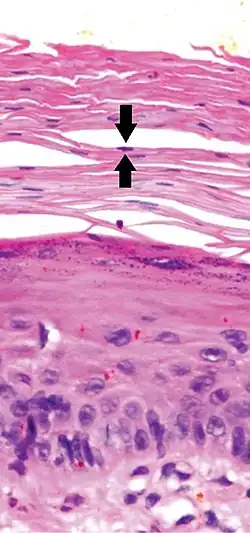

In contrast, hyperkeratosis (pictured) may also show a heterogeneous stratum corneum, but a preserved granular layer is seen.

Parakeratosis is a mode of keratinization characterized by the retention of nuclei in the stratum corneum.[1] In mucous membranes, parakeratosis is normal.[2] In the skin, this process leads to the abnormal replacement of annular squames with nucleated cells. Parakeratosis is associated with the thinning or loss of the granular layer and is usually seen in diseases of increased cell turnover, whether inflammatory or neoplastic. Parakeratosis is seen in the plaques of psoriasis and in dandruff.